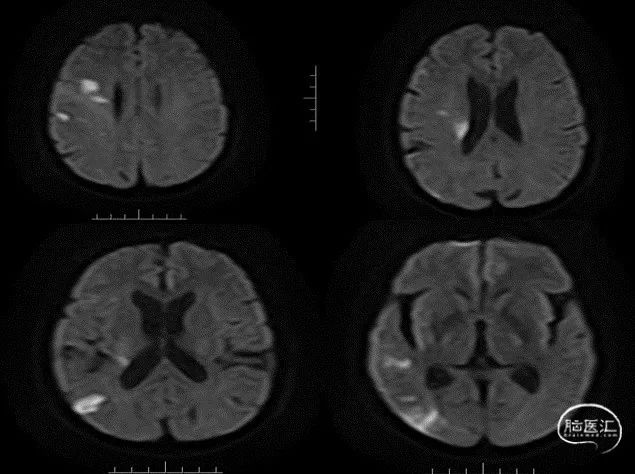

入院影像检查

MRI+DWI

重要影像结论:右侧放射区、右侧基底节区、左侧额叶近大脑镰处多发急性梗死。

重要影像结论:右侧颈内动脉岩骨段管腔内不清晰,眼动脉段远端管腔较对侧明显缩小。

DWI

重要影像结论:右侧额颞枕顶叶多发急性期脑梗死灶。